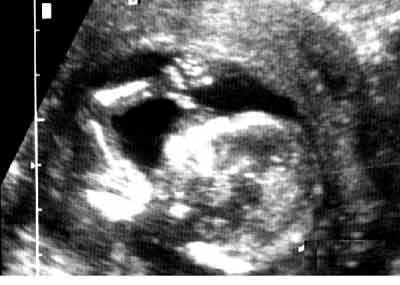

Membres supérieurs : 3 segments